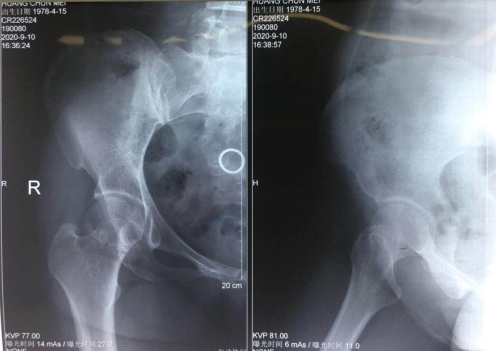

患者黄大姐,44岁,骑电动车上班途中被一辆摩托撞倒,感觉右髋部肿痛,不能活动,在当地医院摄片示“右股骨颈骨折”,被送到betway在线登陆就诊。

黄大姐的情形需要接受手术,讨论后,创伤骨科任海东主任周立国朱宏医生团队决定采用天玑骨科机器人微创治疗股骨颈骨折。“这是一种创伤最小、损伤最低、对患者未来生活最有利的治疗方式。”

9月12日,完善的术前准备后,手术进行,先牵引复位骨折满意,天玑机器人定位,运动灵活、操作稳定的机械臂开始精准建立手术通道,屏幕上,不仅清晰明了地显示患者的骨折位置、规划手术路径,还实时跟踪显示手术情况。手术医生按规划好的进针点,切下1厘米切口,沿着套筒钻入导引针,确认位置无误后,置入3枚空心加压螺钉固定,手术顺利结束。手术切口仅1厘米,出血只有10毫升。